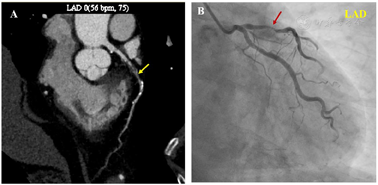

为进一步明确病变性质及全身情况,行18F-FDG PET/CT全身显像(图1A),见左室前壁近心尖、心尖部、间壁近心尖及下壁近心尖局灶性异常摄取,最大标准摄取值(SUVmax)5.0,符合LAD支配区域,疑伴CAD。CTA示:LAD多发钙化、非钙化斑块,管腔明显狭窄,最狭窄处约68%(图3A);左回旋支(LCX)及右冠状动脉(RCA)管壁多发钙化,管腔不明显狭窄。追问病史了解到患者近2年来反复出现活动后胸闷不适,位于心前区,休息数分钟后即缓解,未予重视。遂行运动负荷及静息MPI(图2)示左室前壁近心尖、心尖部、下壁近心尖及间壁近心尖(LAD供血区域)重度可逆性心肌缺血。后行CAG:LM:未见明显狭窄。LAD:近中段90%狭窄,远端血流TIMI0~1级。LCX:近段斑块浸润30%狭窄,远段50%狭窄。RCA:全程斑块浸润,近中段及中远段50%狭窄。综上,临床考虑为LAD严重狭窄至心肌缺血,诊断为CAD。